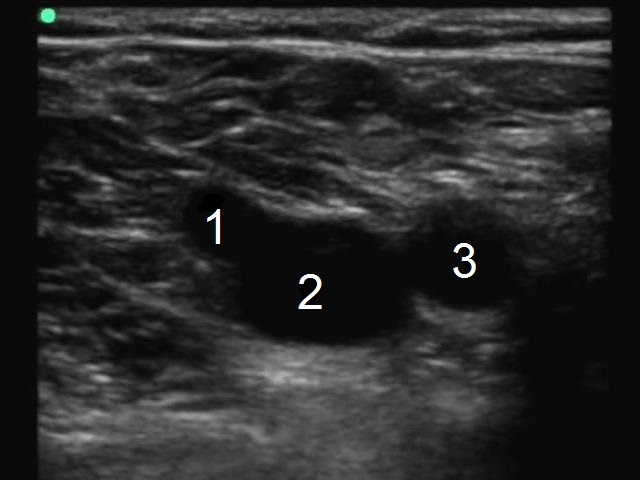

深部静脈血栓症 (DVT) 一般的な大腿静脈 (CFV) 一般的な大腿動脈 (CFA) 大伏在静脈 (GSV) ジャンクション画像

1. 大伏在静脈 (GSV) ジャンクション

2. 大きい大腿静脈 (GFV)

3. 総大腿動脈(CFA)